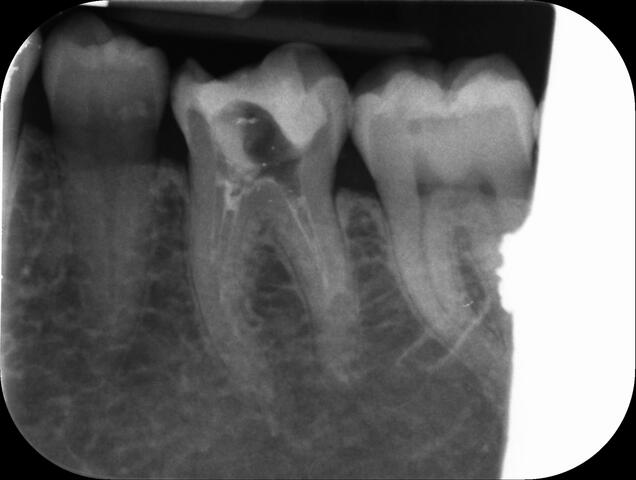

I am pleased to take endodontic referrals. Curved canals >30 degrees and potentially greater than 50 degrees can be negotiated. Sclerosed canals accessed. Post spaces prepared and the patient returned to you ready to restore.In most cases existing crowns, bridges and veneers can be retained with the endodontic access aesthetically restored after the full canal network has been treated.In the first instance I would prefer a radiograph and a brief list of patient expectations and a tooth history.

I really enjoy undertaking root canal treatments - rising to the challenge and helping people out of dental pain for the long term.I was privileged to be asked to speak at the 2016 BDA Conference, where I have a lecture about providing quality endodontic outcomes to patients, working as a generalist. Avoiding problems and pitfalls and maximising efficiency. One of the main matters that he covered was understanding that what is seen on plane radiography is utterly misleading and should not be the criteria by which a generalist continues treatment once it has been started.

At the 2016 BDA Conference, Thomas spoke about providing quality endodontic outcomes to patients, working as a generalist. Avoiding problems and pitfalls and maximising efficiency. One of the main matters that he covered was understanding that what is seen on plane radiography is utterly misleading and should not be the criteria by which a generalist continues treatment once it has been

started.